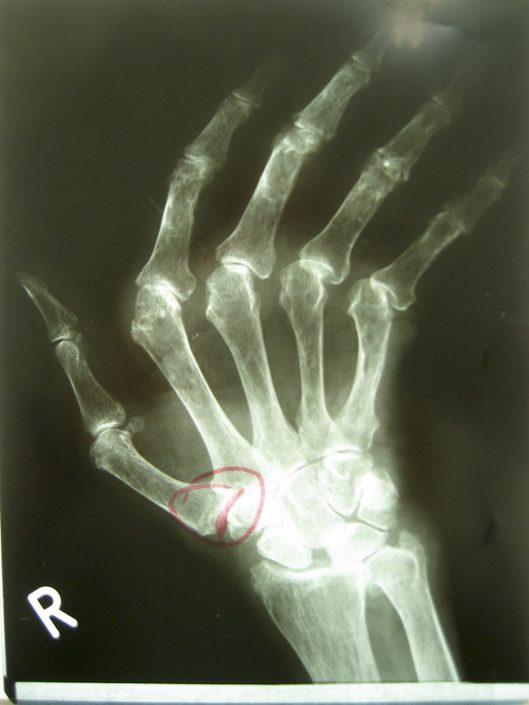

Chronische Polyarthritis

– eine Erkrankung bei der auch häufig die Hände mitbetroffen sind –

Ein typisches Fallbeispiel!

Vermehrt führt bei dieser Erkrankung die Fehlstellung der Fingergrundgelenke zu einer erheblichen Funktionseinschränkung, bedingt durch die Abweichung der Finger. Endstadium ist, dass nur noch eine Greiffunktion mit dem Daumen zum Zeigefinger möglich ist.

Antiulanr-Deviationsorthese

Die vier Langfinger weichen in ihren MP-Gelenken nach lateral ab (Fehlstellung).

Palmarflexionskontraktur – erweitertes Krankheitsbild, Greiffunktion erheblich eingeschränkt!